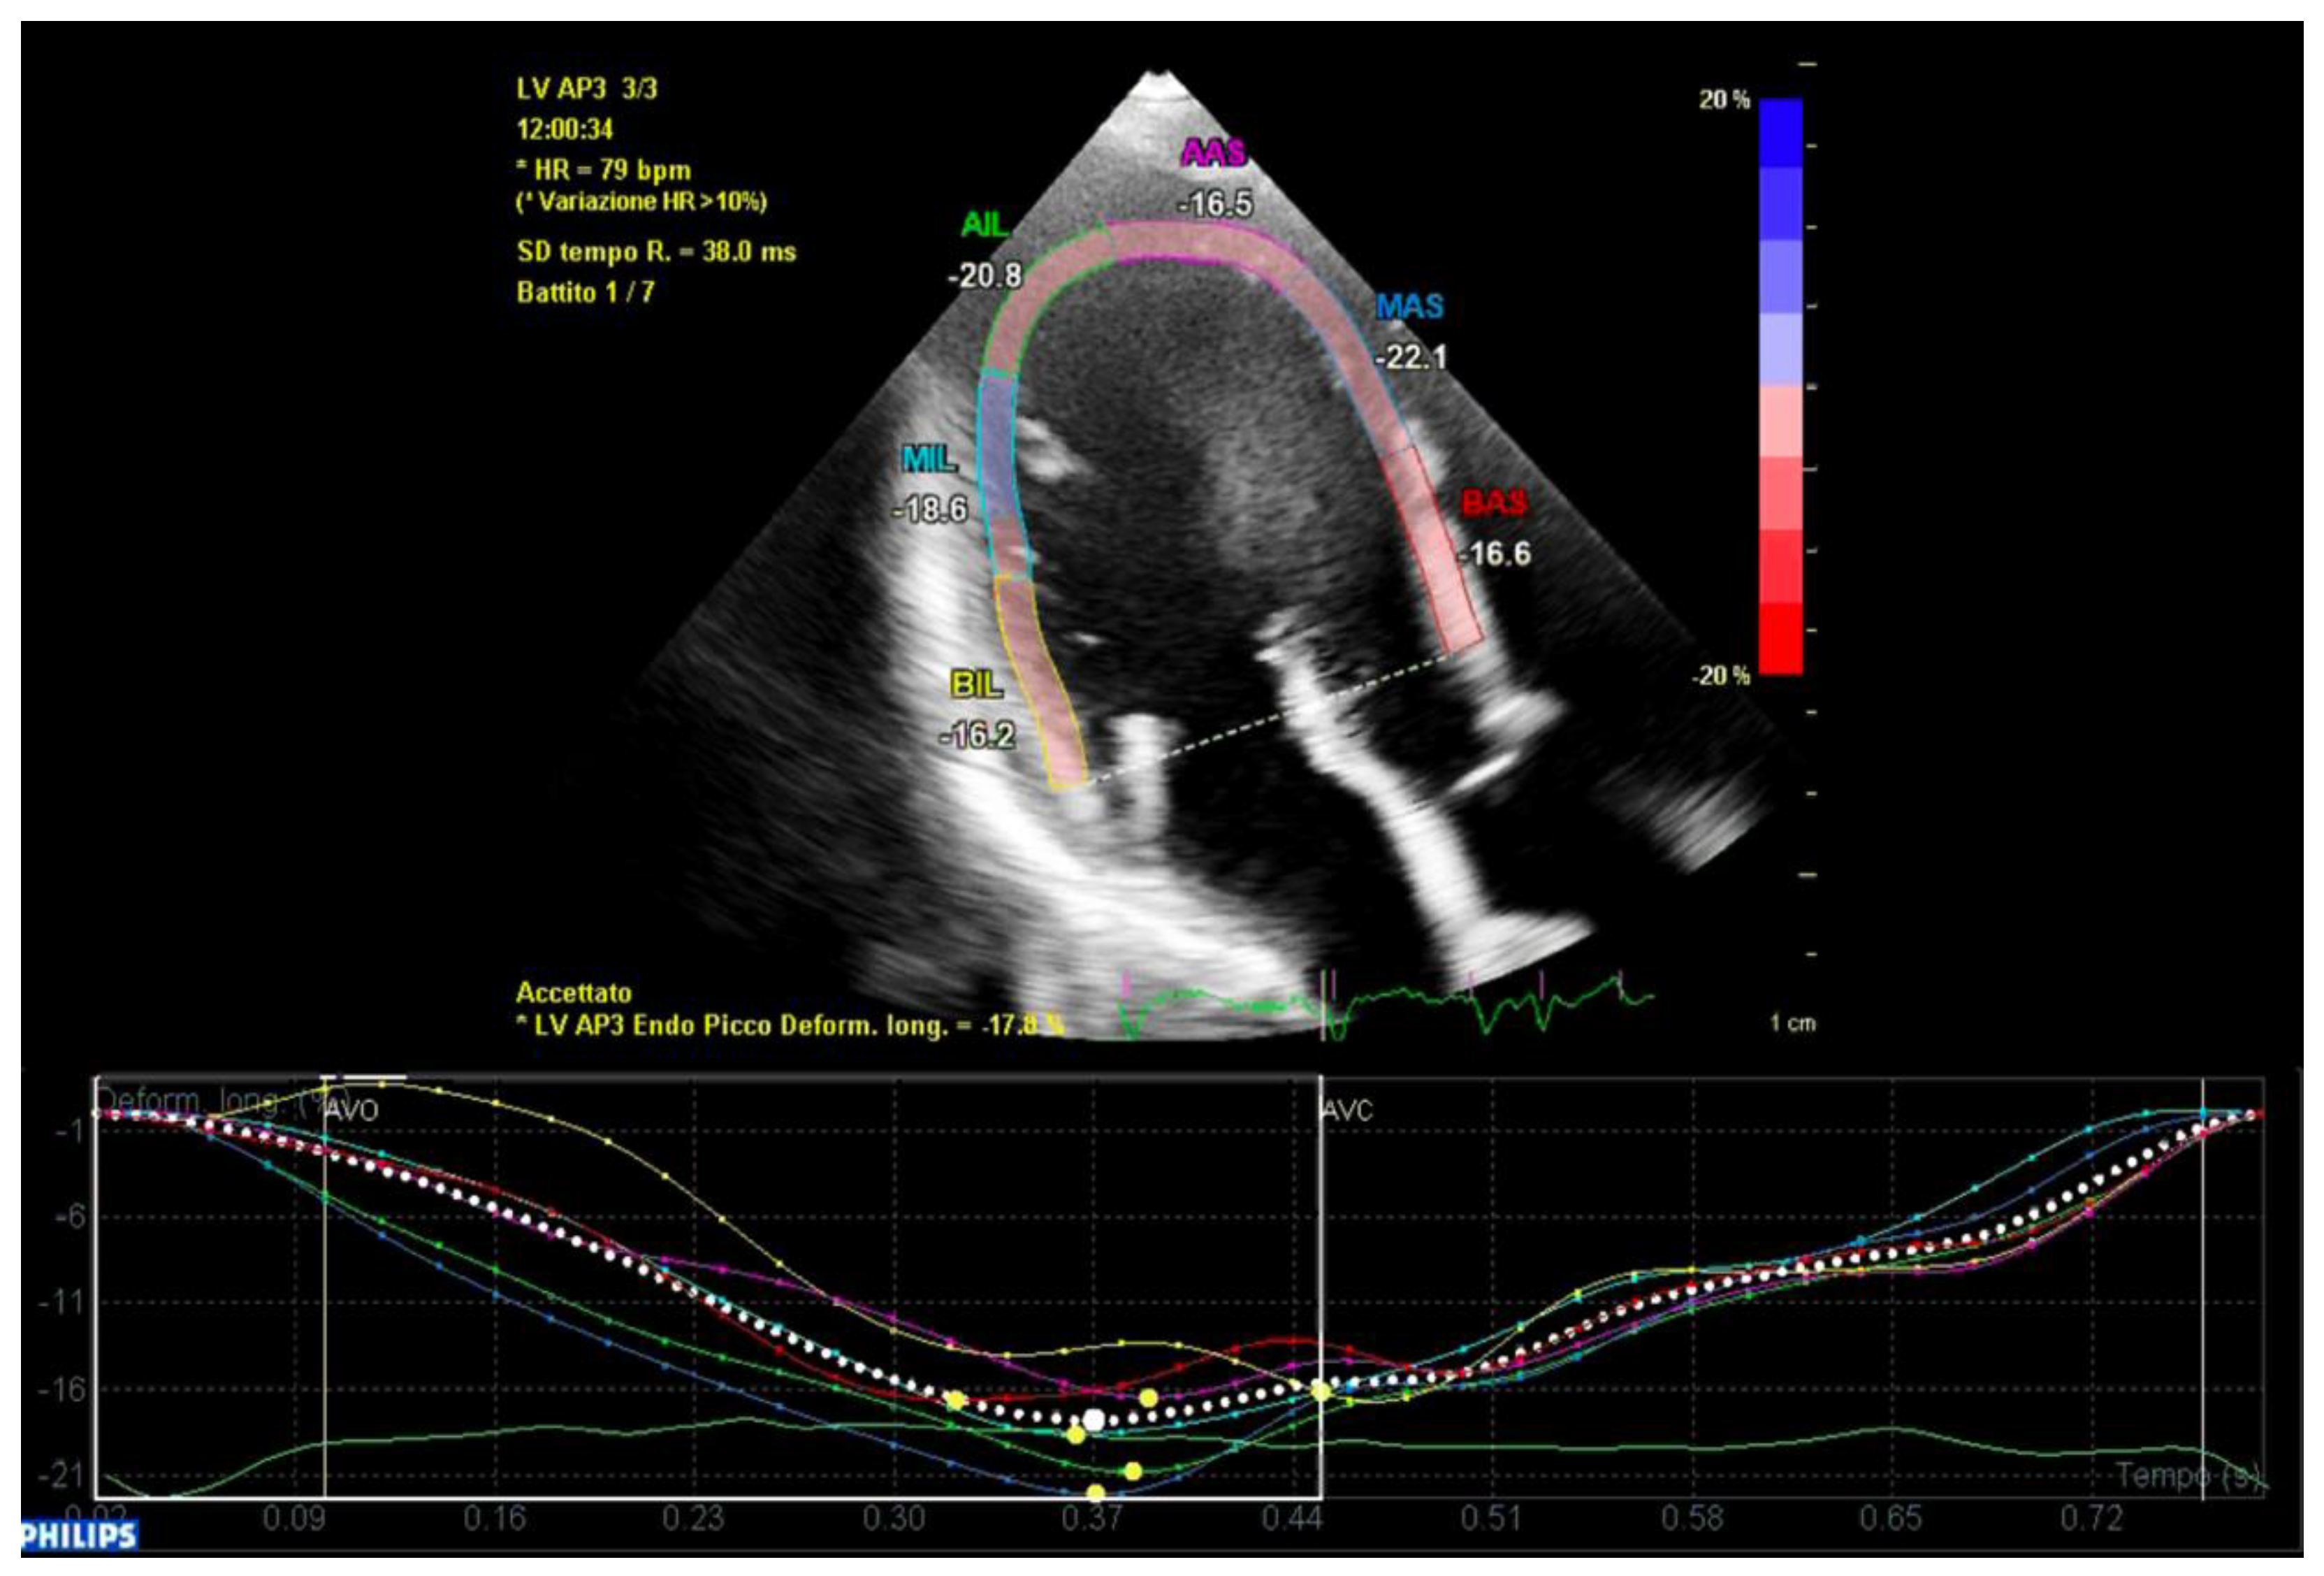

All of the patients underwent transthoracic echocardiography with ECG tracing. Echocardiography was performed using a Philips EpiQ CvX 7C echocardiograph with a Philips X5-1 3D probe. Every patient was screened with basal echocardiography, with careful morphological evaluation of the mitral valve (MV) and grading of the mitral regurgitation (MR) [13], along with a specific protocol to investigate tissue Doppler imaging of the mitral annulus, 3D imaging of the mitral valve and 3D full volume reconstruction of the ventricle. Bileaflet MVP was defined as the prolapse of both leaflets into the left atrium above the mitral annulus by at least 2 mm during the end-systole period, which is visualized in parasternal long axis view (PLAX), as shown in Figure 1 [14]. Mitral valve leaflets’ thickness and length were measured with 2D imaging in PLAX in meso-diastole, whereas the maximum height of the prolapse was measured during the end-systole period. Leaflet thickness was measured in diastole at the thickest point of the leaflet. Leaflets were defined myxomatous based on their morphology and thickness (greater than 5 mm). Antero-posterior and inter-commissural diameters of the mitral valve annulus (MVA) were measured in 2D in PLAX and in A2C views, respectively, both during the diastole and end-systole periods to investigate the presence of paradoxical systolic annular expansion [15]. Antero-posterior and inter-commissural diameters were also measured with 3D imaging, along with the MVA circumference and area. The anterior mitral leaflet (AML) length/AP diameter ratio was also calculated [13]. All of the anatomical parameters were tested at the baseline and after an adjustment for Body Surface Area (BSA). The Tissue Doppler Pulsed Wave (TDI-PW) was measured with an effort to optimize the ultrasound beam alignment with the longitudinal motion of the MVA on both the basal left ventricular segments displayed in the apical 4 chambers view (A4C), apical 2 chambers view (A2C) and apical 3 chambers view (A3C), thus providing 6 tracings for each patient. In this article, we refer to the “spiked systolic high-velocity signal” described by Muthukumar et al. as S3 [16], example shown in Figure 2. Absolute values of S1, S2 and S3 waves were measured. Mechanical dispersion was measured using the TDI, speckle tracking and Electro-Mechanical Window (EMW). The time from the onset of the R wave to the onset of the S1 wave, the end of S2/S3 wave, and the peak of S3 wave were measured using the simultaneous ECG monitoring to assess the presence of dyssynchrony by calculating the standard deviation of each time in all of the six TDI pulsed wave Doppler tracks within the same patient [17]. The speckle tracking (STE) analysis was performed on the workstation using the software CMQ 10 for Q-LAB, and global longitudinal strain (GLS) was calculated using the A4C, A2C and A3C views with a good display of the endocardial border. The endocardial border was outlined by a single operator at the end-diastolic phase of the cardiac cycle. Minor adjustments were made to optimize tracking throughout the cardiac cycle. Mechanical dispersion (MD) was calculated as the standard deviation (SD) of the times measured from the onset of R on the ECG to the peak strain (TPS) in each of the 18 segments of the left ventricle, and sub-analyses were performed separately considering the basal segments alone, the mid-ventricular segments alone, the apical segments alone and basal segments combined with middle segments as well. The transversal shift measured by CMQ 10 using Q-LAB software was analyzed as well in order to quantify the transversal motion of the ventricular walls throughout the cardiac cycle. Additionally, the GLS pattern was analyzed to research a specific double peak pattern that is suggestive of arrhythmic events and dyssynchrony.

In conclusion, the variables that were identified as the predictors of major arrhythmic events with the highest AUC (>0.80) within our high-risk population of arrhythmic MVP patients were the AML length (measured as shown in Figure 7), the S3 of the inferolateral basal segment and the mechanical dispersion of the basal and mid-ventricular segments calculated with speckle tracking analysis (Figure 8 and Figure 9).

Figure 8. Mechanical dispersion in a patient from the ICD-MVP group. The segments that present greater peak systolic shortening time dispersion are the anterior-septal basal segment (in red) and the inferolateral basal segment (in yellow). Apical segments present a synchronous peak systolic shortening.